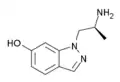

AL-34662 | 1-((S)-2-Aminopropyl)-1H-indazol-6-ol | 210580-75-9 |